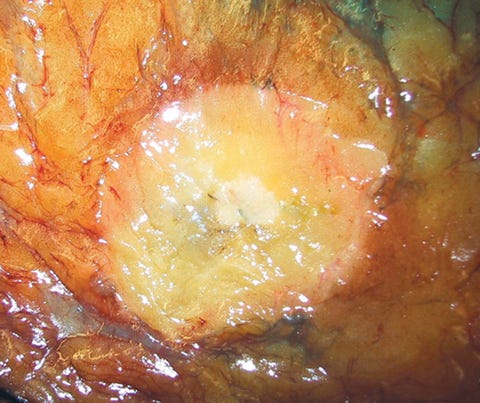

Infiltrating duct carcinoma (IDC) of no special type - microscopic images

The premalignant precursors of invasive duct carcinoma of no special type are DCIS (ductal carcinoma in situ) and classic LCIS (lobular carcinoma in situ). In addition, we speculate that there may be unidentified precursors based on molecular patterns of change without microscopic changes, although this is unproven.

Precursor of IDC - ductal carcinoma in situ (DCIS)

Ductal carcinoma in situ (DCIS) is a neoplastic proliferation of breast ductal epithelial cells within the ductal-lobular system with malignant microscopic features but without evidence of invasion through the epithelial basement membrane or myoepithelial cell layer into the surrounding stroma.

DCIS is a precursor of infiltrating duct carcinoma of no special type. It is also a precursor of tubular carcinoma, cribriform carcinoma, male invasive carcinoma and neuroendocrine carcinoma-small cell type.

DCIS includes a heterogeneous group of lesions in terms of microscopic appearance, molecular alterations, biomarker expression profile and biologic potential for progression to invasive carcinoma. It is divided into low grade (less aggressive) DCIS and high grade DCIS. Normal breast tissue appears to transform to only one of these entities through two distinct molecular pathways (i.e. high grade DCIS does not typically arise from low grade DCIS). Low grade DCIS shows frequent chromosomal losses at 16q. High grade DCIS shows frequent losses at 8p and gains at 17q and has a similar molecular profile as invasive breast cancer.

The microcalcifications that identify DCIS on mammograms are a response to cell death from either a hypoxic environment (the Warburg effect) or cell crowding due to abnormal cells growing unchecked inside the duct. When these calcifications appear on a mammogram, they often have suspicious features that require further investigation.